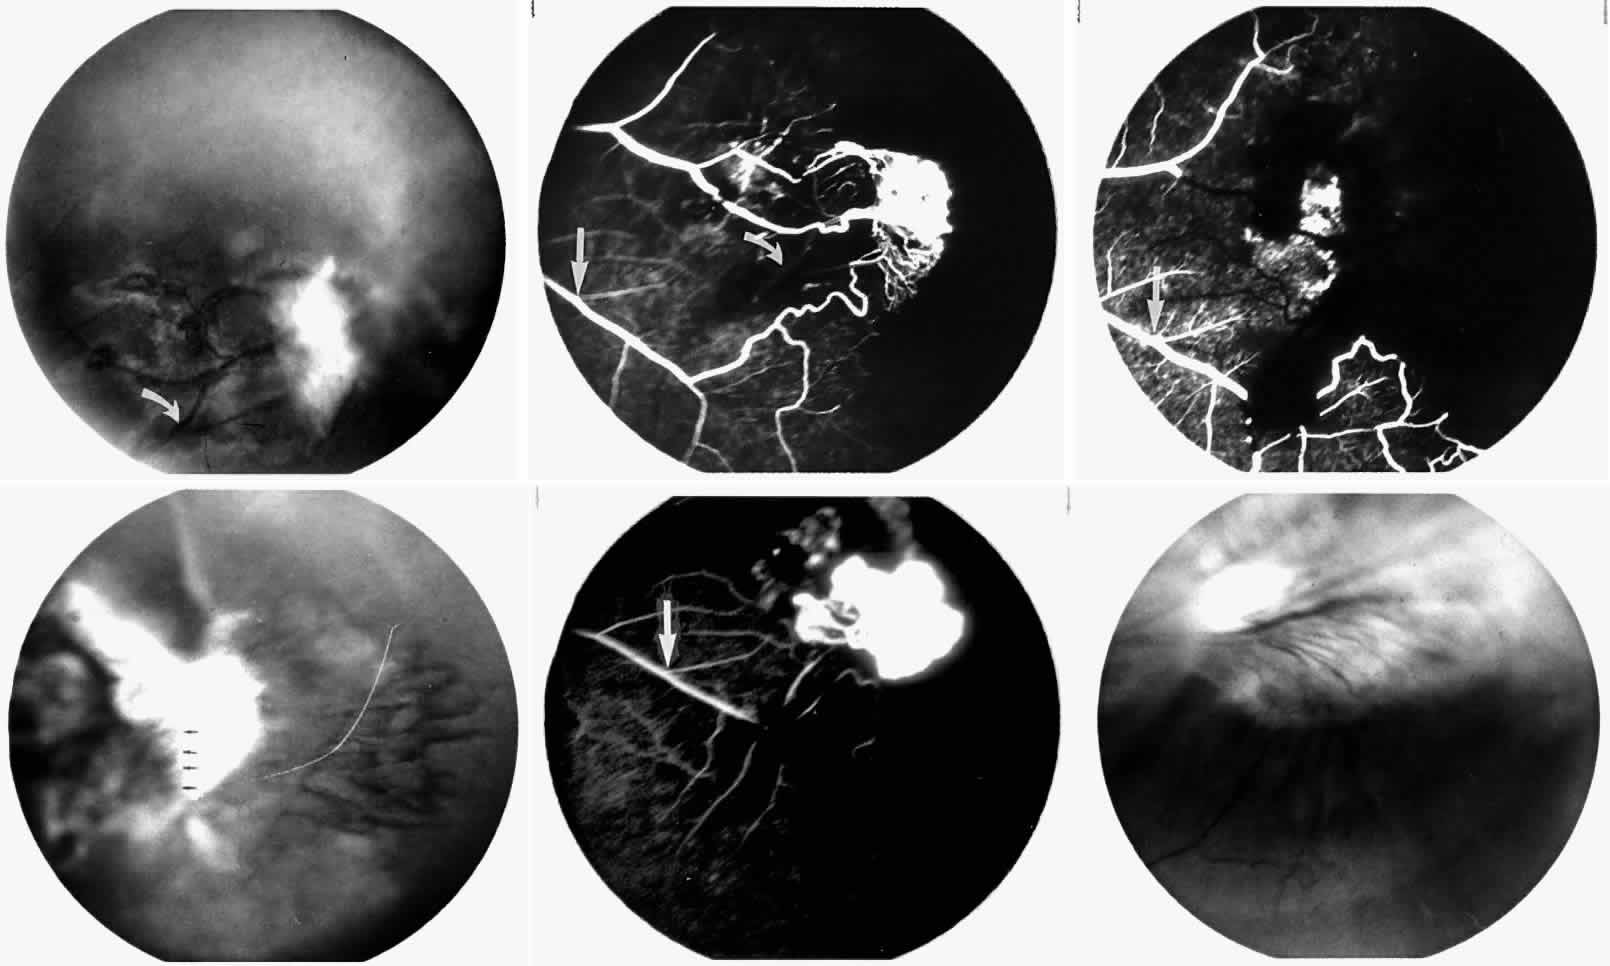

STAGE III: PRERETINAL NEOVASCULARIZATION (PROLIFERATIVE SICKLE RETINOPATHY). “Sea fan”-shaped neovascularization typically develops on the venular side of an arteriolar-venular anastomosis, mimicking the normal development of retinal capillaries (Fig. 24).125 A lowered oxygen tension and angiogenic factors released on the venular side may be the stimulus for neovascular growth.125,126 In most instances, the direction of growth is toward the ora serrata, from the perfused retina toward the nonperfused retina. Presumably, this represents an abortive attempt to revascularize the nonperfused retina, initiated by vasoproliferative factors.

Fig. 24. A. Photograph of the peripheral retina, demonstrating several small fibroglial membranes. B. Fluorescein angiogram corresponding to A, showing multiple arteriolar-venular anastomoses with early sea fan formation. C. Photograph of the same area 2 years later demonstrates more fibroglial membranes. D. Fluorescein angiogram corresponding to C shows new sea fans caused by an arteriolar-venular anastomosis (curved arrow). Large arrow (A through D) identifies corresponding arteriolar bifurcation.

The characteristic neovascular lesions of PSR are called sea fans because they resemble the marine invertebrate Gorgonia flabellum.70 They tend to occur more commonly in the temporal periphery, but they have been reported to occur in the temporal macula in the presence of extensive nonperfusion.130,133 Initially they grow on the surface of the retina, but they often become elevated into the vitreous and adhere to a partially detached posterior hyaloid.114 It may be difficult to visualize small sea fans ophthalmoscopically; however, fluorescein angiography clearly demonstrates leakage of dye into the vitreous (Fig. 25). The feeding arteriole is usually more tortuous than the draining venule (Fig. 26). Early on, the neovascular lesion is fed by a single arteriole and drained by a single venule, but with time, additional arterioles and venules become arborized within the lesion (Fig. 27).129 Growth of the sea fan often occurs circumferentially, rather than radiallyÜmh- 1Ý, toward the ora serrata. Progressive circumferential growth may lead to neovascular lesions extending around the entire periphery. As it matures, a white fibroglial mantle often covers the neovascular tissue (Color Plate 2B).

Fig. 25. Fluorescein angiogram of early proliferative sickle retinopathy arising from an arteriolar-venular anastomosis in an area of irregular peripheral capillary border. Note that this area of qualitatively abnormal peripheral capillary border is in the same eye with a qualitatively normal peripheral retinal vasculature, as demonstrated in Figure 23.

Fig. 26. A. Arterial filling phase of the fluorescein angiogram of a sea fan demonstrates tortuosity of the feeding arteriole. B. Early arteriolar-venular filling phase demonstrates straightening of the draining venule. Note that this sea fan is adjacent to the qualitatively normal peripheral retinal vasculature demonstrated in Figure 23.

Fig. 27. A. Photograph of sea fan neovascularization with hemorrhages at the margins and a white line demarcating perfused and nonperfused retina. B. Fluorescein angiogram shows multiple feeding arterioles and draining venules.

PSR is associated with the severe vision-threatening sequelae of sickle cell disease: vitreous hemorrhage (stage IV) and retinal detachment (stage V). These stages are believed to result from transudation of blood components into the vitreous through the incompetent neovascular tissue (Fig. 28). Vitreous fluorophotometry has quantified the leakage from the peripheral neovascularization.134 This leads to premature syneresis and collapse of the vitreous, inducing tractional forces on the retina that lead to vitreous hemorrhage, retinal tears, and tractional and rhegmatogenous retinal detachment. In rare cases, an exudative detachment may occur.